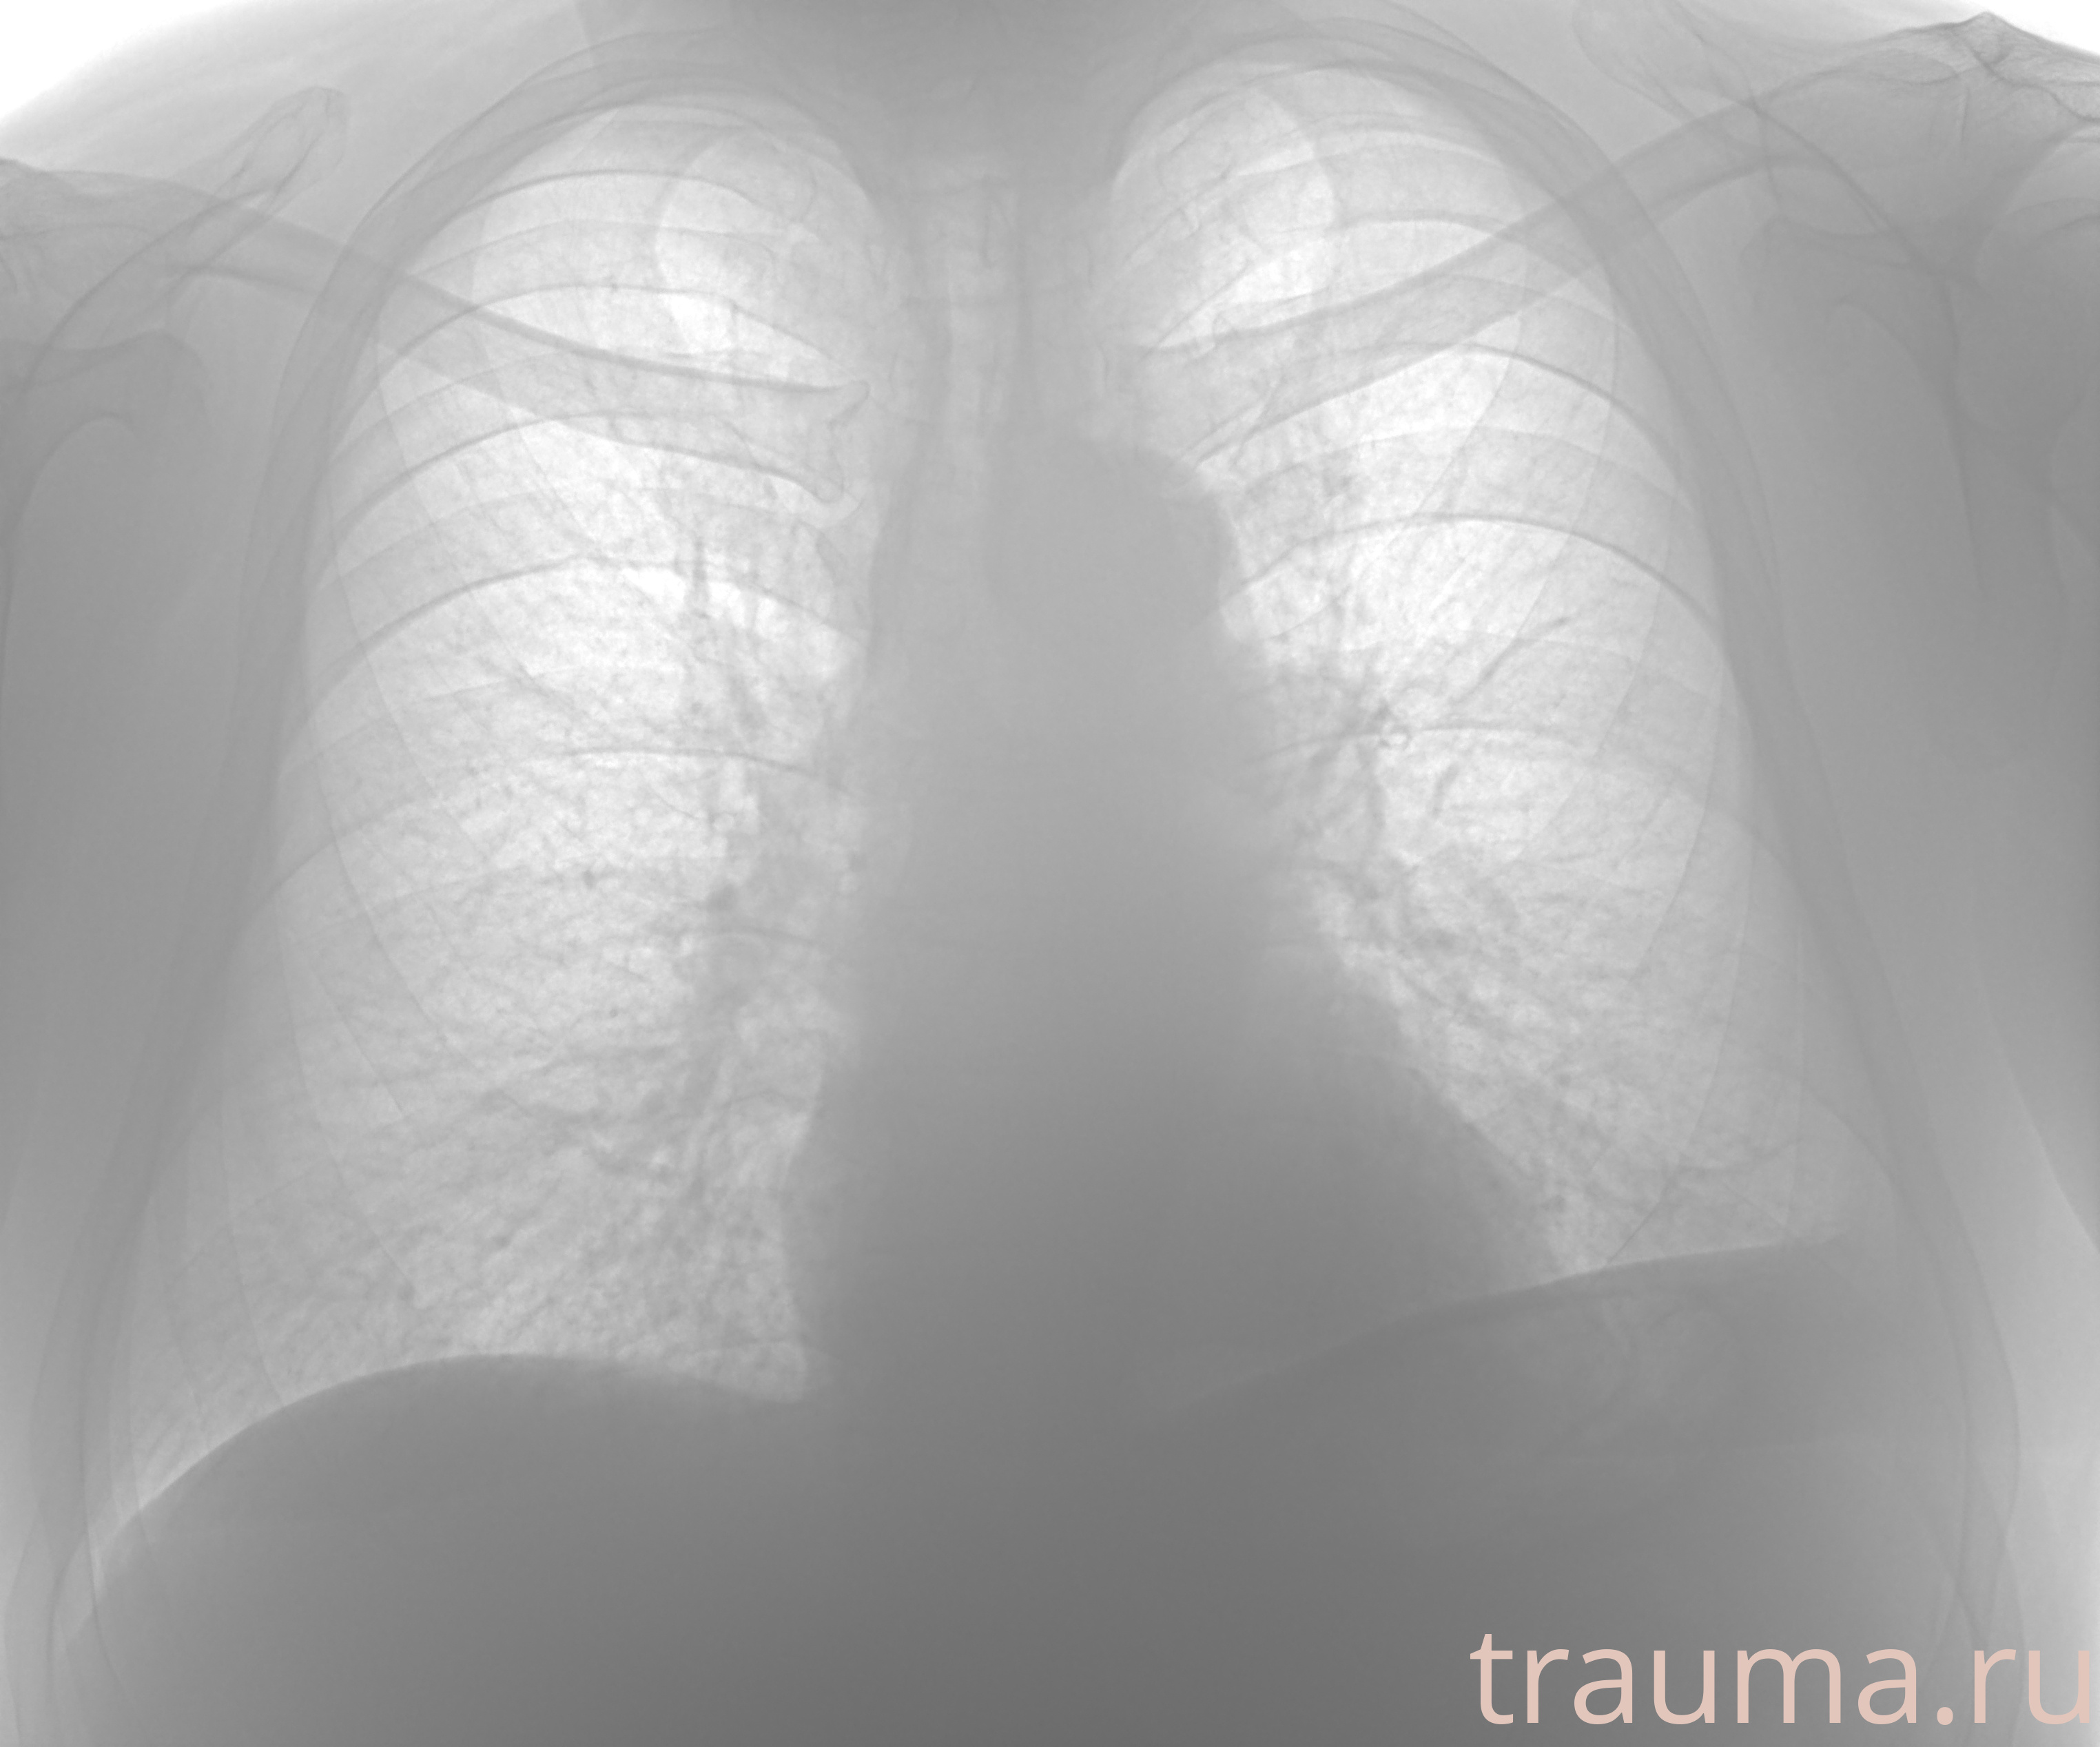

Рентгенограммы

Рентген на дому: по вашему адресу приезжает врач-рентгенолог, травматолог-ортопед с мобильным рентгеновским аппаратом, проводит диагностику травмы или заболевания, делает необходимые рентгенограммы, дает рекомендации по дальнейшему лечению. Получить качественные снимки в домашних условиях возможно благодаря уникальной методике, разработанной МосРентген Центром для института  Склифосовского

при переломе шейки бедра и пневмонии от компании МосРентген Центр - партнера Института имени Склифосовского